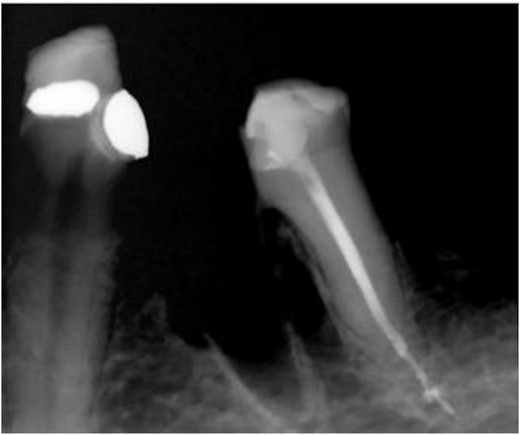

Hemisection and removal of the mesial root were performed under local anesthesia. Hemisection was chosen because the lesion involved only one root, while the remaining distal root had sufficient alveolar bone support. The tooth also had strategic value as a terminal abutment, critical for maintaining stable occlusion. A full-thickness flap was elevated on the buccal and lingual aspects. Using a low-speed surgical fissure carbide bur under normal saline irrigation, a vertical cut was made to separate the tooth. The mesial root was elevated and removed, and granulation tissue in the mesial socket was curetted. The socket was irrigated with sterile saline, and the flap was approximated and sutured with Vicryl 4–0 sutures (Fig. 9). The occlusal table was minimized to direct forces along the long axis of the distal root. Immediate postoperative radiographs confirmed the stable retention of the distal root (Fig. 10).

Immediate postoperative radiograph of the mesial segment of tooth 36 showing overhanging dentin at furcation area mesial to the remaining root.